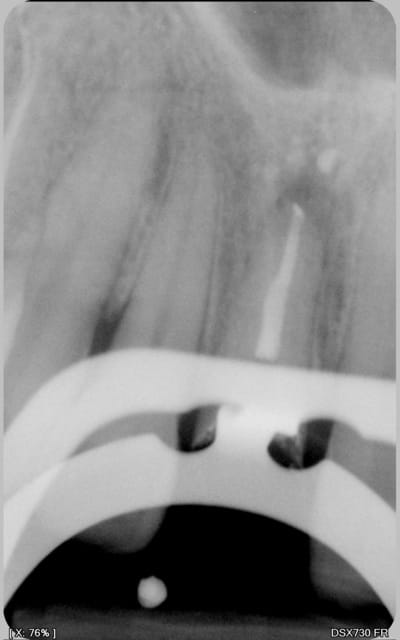

Re-belotte. 15.

et un bon vieux mordu, le tout 40 mn productivité !))))

Ca va on le voit bien à l'oeil nu le mv2 ? rendez vous de 30 mn, et oui consult (douleur sous gros amg), un peu just pour faire l'empreinte et la taille dans la séance, dommage . Pas facile de zoomer avec une seule main avec l'iphone par contre !))))